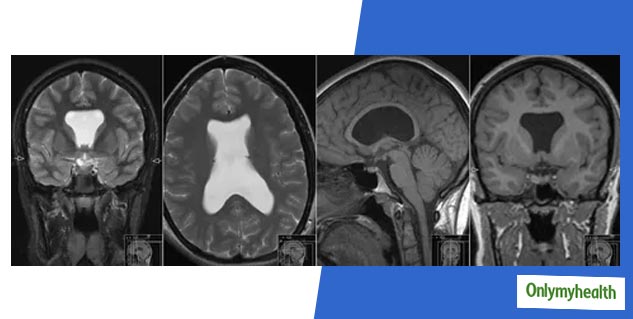

कुछ बच्चे असामान्य व्यवहार दिखाते हैं, जैसे उनमें दृष्टि दोष, संज्ञानात्मक मुद्दे, अटैक आदि समस्याएं होती हैं। यह मस्तिष्क में सेप्टम पेल्यूसीडम झिल्ली की अनुपस्थिति के कारण होता है। सेप्टम पेल्यूसीडम, एक बहुत पतली झिल्ली होती है, जो आकार में त्रिकोणीय होती है। यह मस्तिष्क के दाएं और बाएं लेटरल वेंट्रिकल कुछ भागों को अलग करता है। सेप्टम पेलुकिडियम बाएं और दाएं सेरेब्रल गोलार्धों के बीच मस्तिष्क की मध्य रेखा में स्थित है। यह कोरपस कॉलोसम से नीचे की ओर फॉर्निक्स तक एक शीट के रूप में चलता है। अकेले सेप्टम पेलुसीडियम की अनुपस्थिति एक विकार नहीं है, बल्कि इसके बजाय सेप्टो-ऑप्टिक डिसप्लेसिया वाले बच्चों में यह एक विशेषता है।